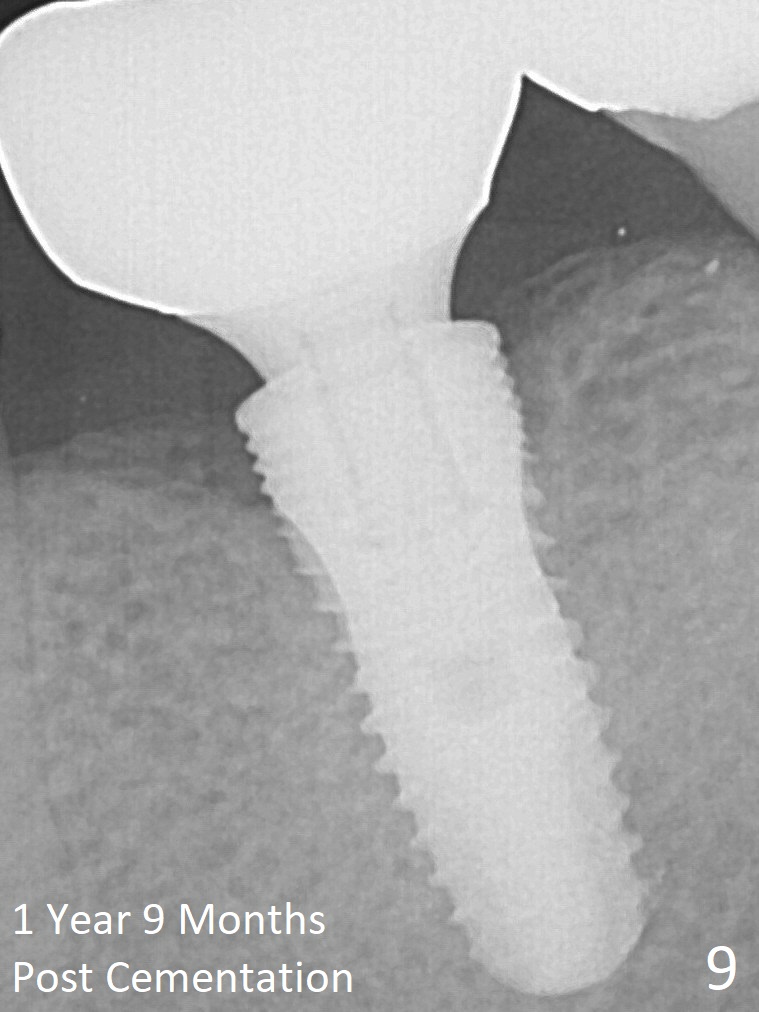

The bony defect appears to be repaired 1 year 9 months post cementation (Fig.9).